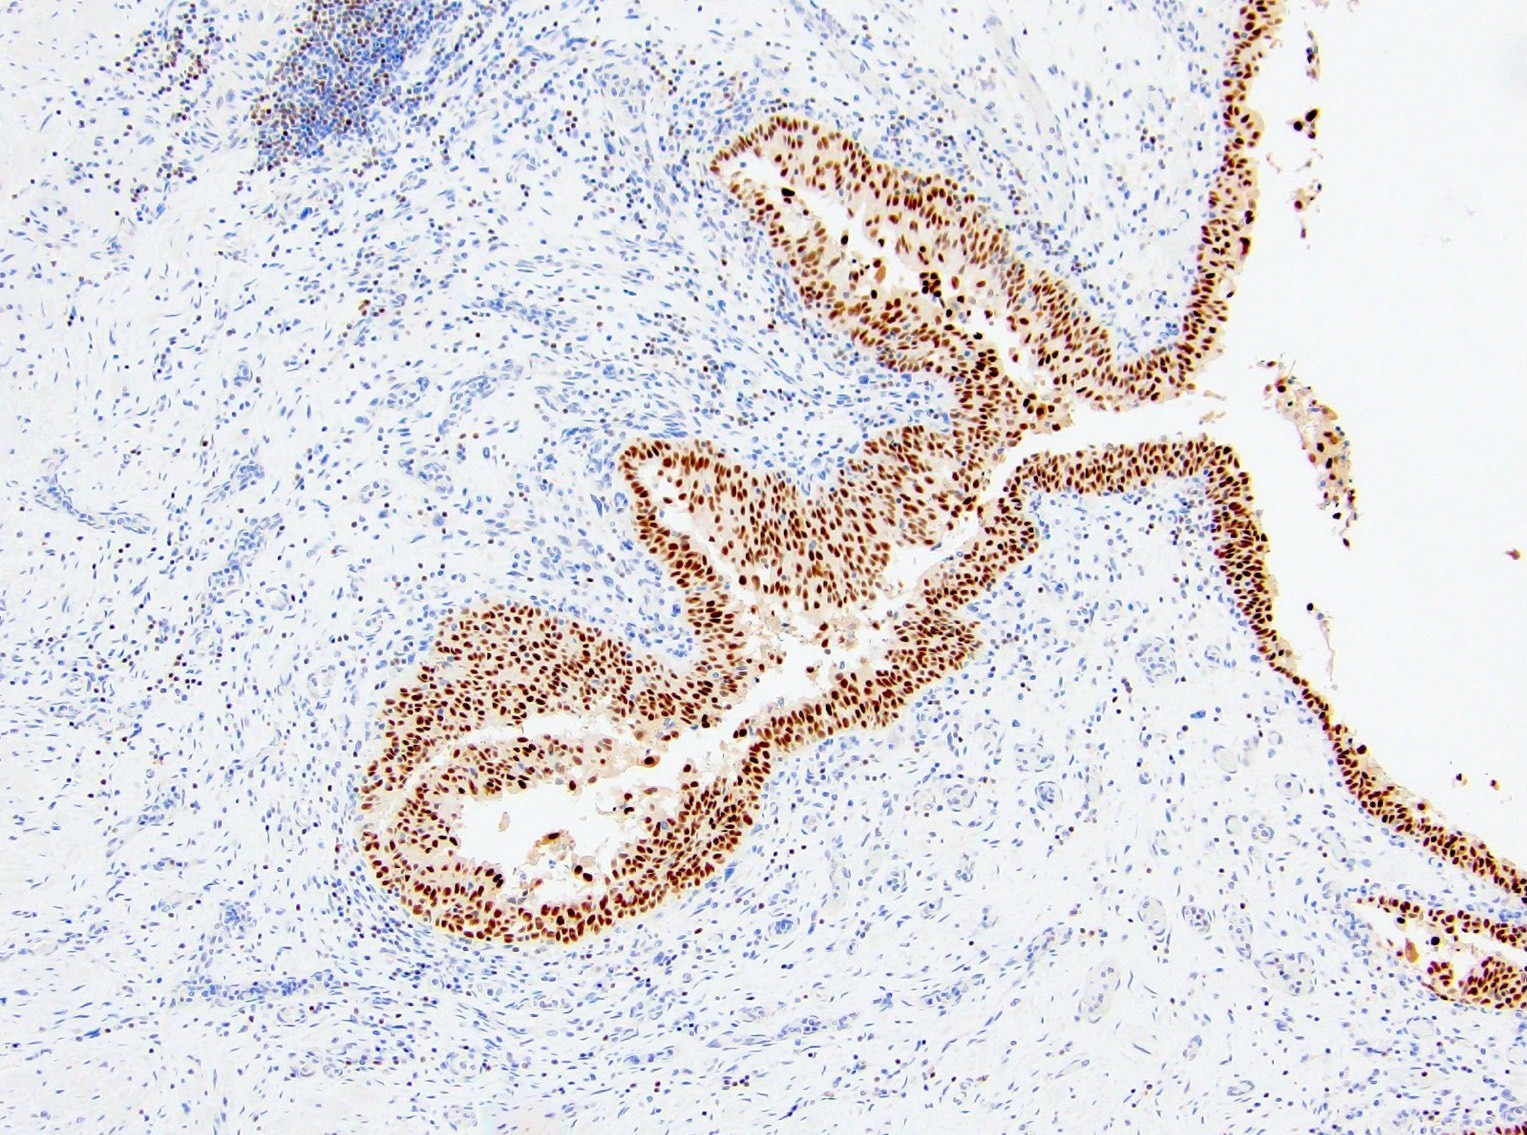

Microscopic (histologic) images

Contributed by Emily S. Reisenbichler, M.D., Andrey Bychkov, M.D., Ph.D., Maria Tretiakova, M.D., Ph.D. and Debra Zynger, M.D.

Positive staining - normal

Positive staining - tumors